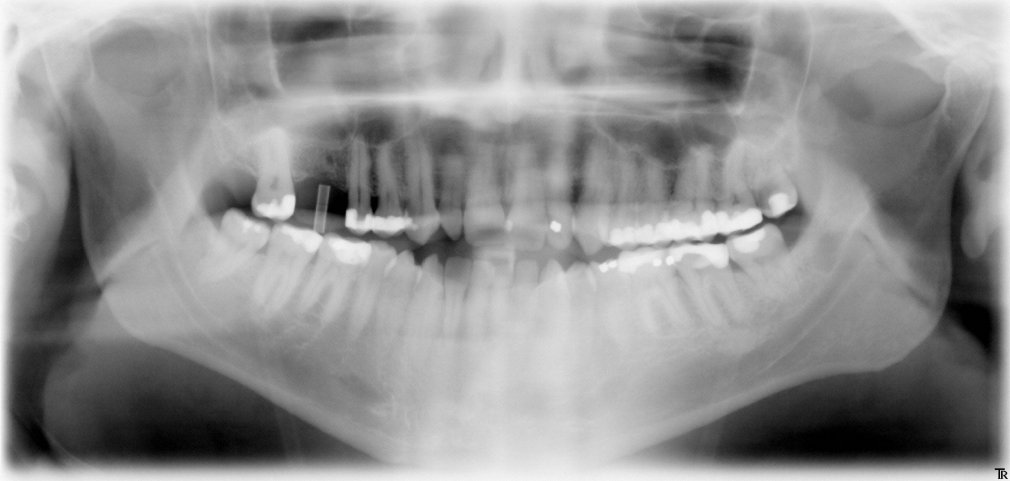

Panorama-Röntgenaufnahme

Implantat im Oberkiefer

Die reale Knochenhöhe wird mit Hilfe einer Tiefziehschiene mit eingearbeiteten Metallkugeln ermittelt. Bei digitalen Röntgengeräten kann gegebenenfalls auf die Messaufnahmen verzichtet werden, da sie über ein integriertes Messtool verfügen. Zur Detailabklärung kann es erforderlich sein, zusätzliche Aufnahmen von einzelnen Zahnabschnitten zu machen.